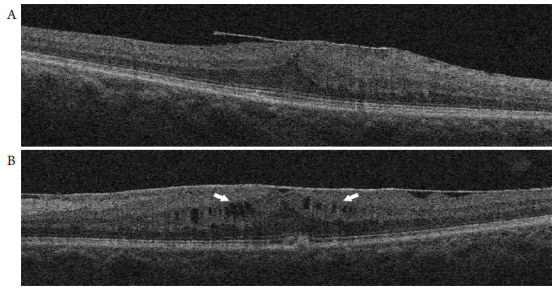

按OCT显示的中心凹处(1 mm)INL中是否存在肉眼可辨的囊样水肿改变将3 7只眼进一步分为两个亚组,即有囊样改变组,共11只;以及无囊样改变组,共26只眼(图2)。

图2 INL层无囊样改变(A)及存在囊样改变(B)的黄斑前膜患者OCT图像,中心凹处INL层存在多个低信号的囊样改变区域(B;白色箭头)